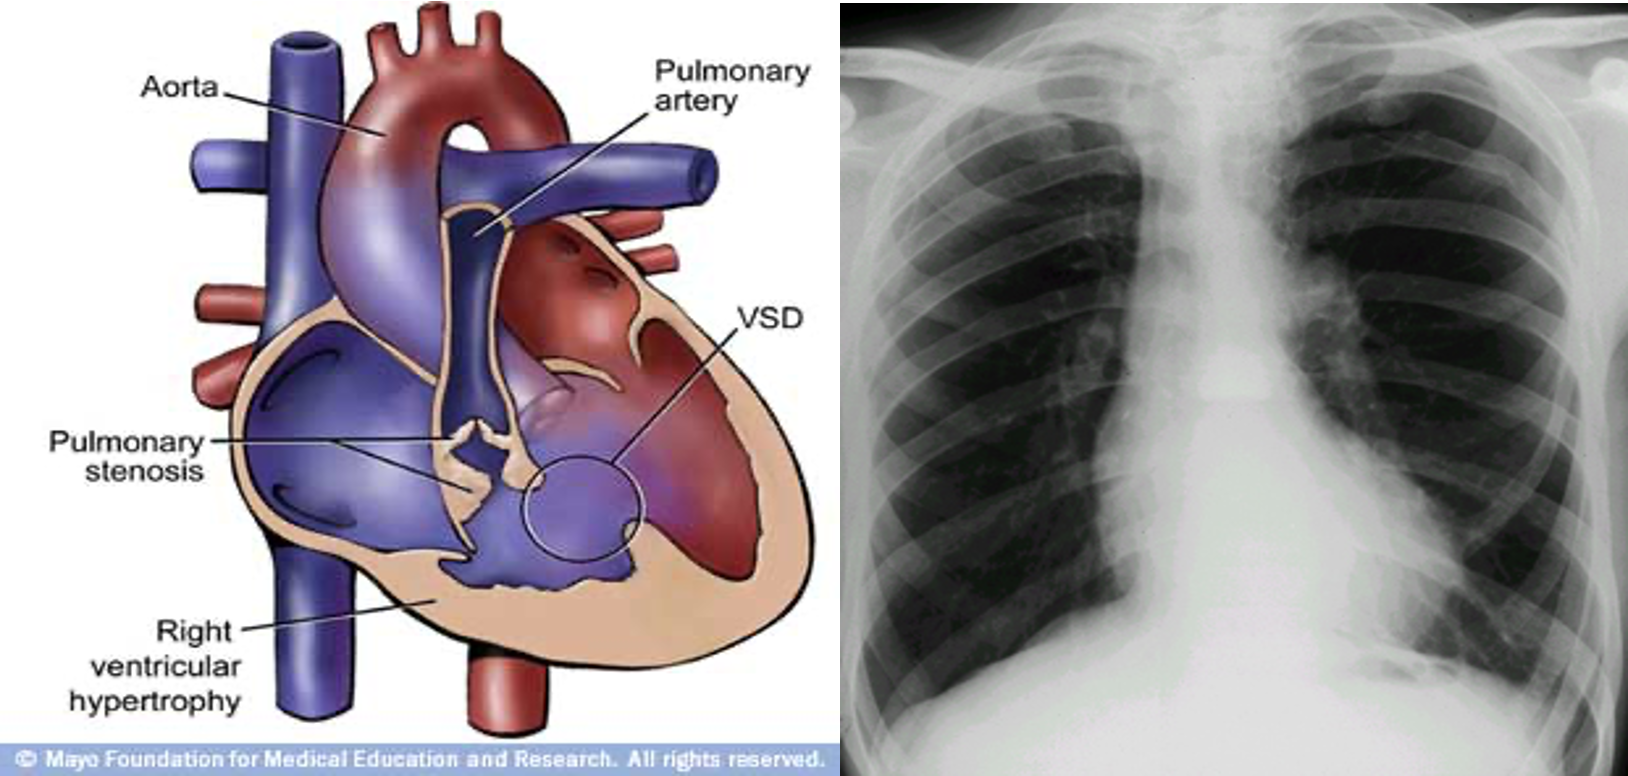

Tetralogy of Fallot

• X-ray

• Boot shaped heart

• Dec PVM

• Right arch